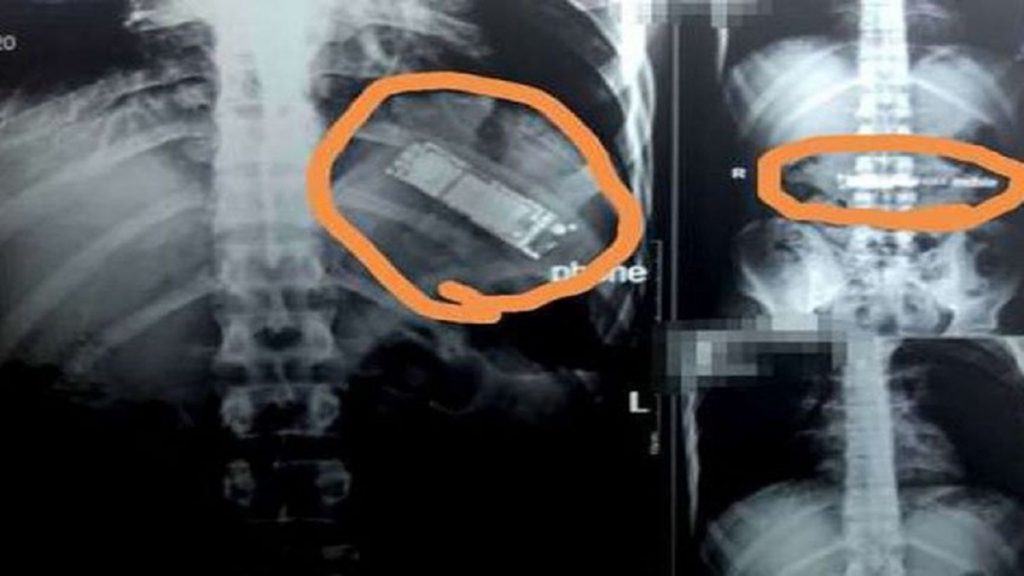

মিসরের রাজধানী কায়রোর একটি হাসপাতালে এক যুবকের পেটে আল্ট্রাসনোগ্রাম করে রিপোর্ট দেখে চিকিৎসকদের চোখ কপালে।

আস্ত একটি মোবাইল ফোন ২৮ বছরের ওই যুবকটির পেটের ভেতর। গত সাত মাস ধরেই এটি পেটের মধ্যেই ছিল। খবর গালফ নিউজের।

দক্ষিণ কায়রোর আল ওয়াটান নামে ওই বেসরকারি হাসপাতালের চিকিৎসক ডা. মো. আল জহোর বলেন, প্রথমে টিউমার মনে করে অস্ত্রোপচারের জন্য আল্ট্রাসনোগ্রাম করা হয়। কিন্তু এতে দেখা যায়, আস্ত একটি মোবাইল ফোনসেট।